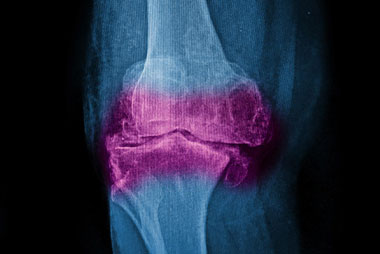

Trauma y Manejo de Fracturas

TALLER DE ESPECIALIZACIÓN Y PERFECCIONAMIENTO

Institución Badra te invita al taller de Trauma y Manejo de Fracturas, dictado por médicos especialistas en Emergentología. El presenta taller pretende abordar, desde el punto de vista de los primeros auxilios, las eventualidades que pueden comprometer la vida del paciente por diferentes fracturas. Los participantes aprenderán a obtener ayuda médica ante una fractura, a hacer uso de férula, las maniobras correspondientes, etc. Te esperamos!

- Clasificación de las fracturas.

- Complicación de las fracturas.

- Luxación.